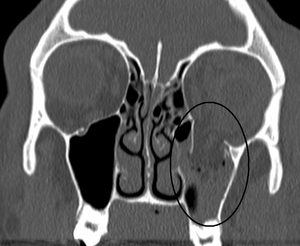

Orbital blowout fracture

| An orbital blowout fracture of the floor of the left orbit. | |

An orbital blowout fracture is a traumatic deformity of the orbital floor or medial wall, typically resulting from impact of a blunt object larger than the orbital aperture, or eye socket. There are two broad categories of blowout fractures: open door, which are large, displaced and comminuted, and trapdoor, which are linear, hinged, and minimally displaced. They are characterized by double vision, sunken ocular globes, and loss of sensation of the cheek and upper gums due to infraorbital nerve injury.[1]

In pure orbital blowout fractures, the orbital rim (the most anterior bony margin of the orbit) is preserved, while with impure fractures, the orbital rim is also injured. With the trapdoor variant, there is a high frequency of extra-ocular muscle entrapment, despite minimal signs of external trauma, a phenomenon referred to as a 'white-eyed' orbital blowout fracture.[2] They can occur with other injuries such as transfacial Le Fort fractures or zygomaticomaxillary complex fractures. The most common causes are assault and motor vehicle accidents. In children, the trapdoor subtype are more common.[3] Reconstruction is usually performed with a titanium mesh or porous polyethylene through a transconjunctival or subciliary incision. More recently, there has been success with endoscopic, or minimally invasive, approaches.[4]

The most commonly fractured area in blowout fracture is the floor of orbit. Diagnosis is based on clinical and radiographic evidence. Periorbital bruising and subconjunctival hemorrhage are indirect signs of a possible fracture. On Water's view radiograph, polypoid mass can be observed hanging from the floor into the maxillary antrum, classically known as teardrop sign, as it usually is in shape of a teardrop. This polypoid mass consists of herniated orbital contents, periorbital fat and inferior rectus muscle. The affected sinus is partially opacified on radiograph. Air-fluid level in maxillary sinus may sometimes be seen due to presence of blood. CT scan can also show any soft tissue and bone involvement. Fracture of medial wall can produce subcutaneous emphysema, especially when blowing the nose or while sneezing. Lucency in orbits (on a radiograph) usually indicate orbital emphysema.